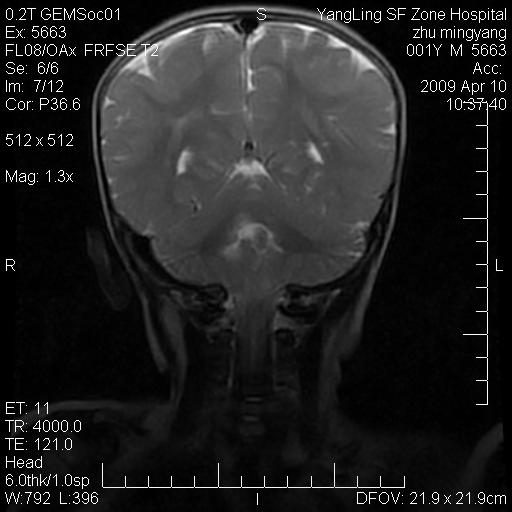

患者:1岁半,两天前外伤收住我院,ct检查小脑占位

考虑星形细胞瘤,建议增强

髓母细胞瘤或血管母细胞瘤,增强后可以鉴别;影像资料见 <。鱼博浪老师的《中枢神经系统ct与mr鉴别诊断》 小脑部肿瘤章节。

髓母细胞瘤或血管母细胞瘤!支持!

支持考虑髓母细胞瘤

考虑----髓母细胞瘤可能性大

考虑髓母细胞瘤或室管膜瘤。

支持髓母细胞瘤。

考虑髓母细胞瘤。

考虑髓母细胞瘤或星形细胞瘤

考虑髓母细胞瘤.

小脑肿瘤.考虑髓母细胞瘤可能.

就病灶部位及临床资料首先考虑髓母.